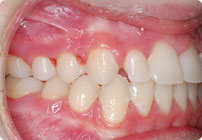

Femenino

Antes

Despues

Caso: 12 años

Adolescente: Clase II

Dental Maxilar Protrusion

Extract U4’s/L5’s

4 series de alambres:

.016″, 022″, .0215″ x .028″, .019″ x .025″ Trenzado

Elástico clase 2 2oz. TP amarillos y verdes

Retenedores: Interior Fijo de TMA y Hawley en superior

Tiempo de tratamiento: 15 Visitas